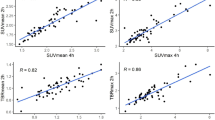

In all the 14 patients, the tumor was visually identifiable from its higher signal intensities than the surrounding lung tissues (Figs. 25.3 and 25.4). Quantitatively, SUVmax, TMR, and TBR were all significantly higher on RG images (1.93 ± 1.11, 1.46 ± 0.78, and 1.42 ± 0.87, respectively) than on NG images (2.09 ± 1.11, 1.61 ± 0.78, and 1.53 ± 0.87, respectively) (Table 25.2, Fig. 25.5).

Whereas the NG images showed tumor hypoxia in three patients, the RG images identified tumor hypoxia in two more patients (i.e., a total of 5 patients). In patients with hypoxia, HV on NG images was 12.8 ± 22.6, whereas that on RG images was 13.2 ± 22.7, which was significantly higher (Table 25.3).

The results of this study showed significant differences in various quantitative values between RG and NG. Theoretically, RG is less affected by motion artifacts, and thus the images acquired with RG are considered to be more accurate than those with NG. Our data suggest the risk of using non-respiratory gating for FMISO PET in NSCLC, because non-respiratory gating could significantly underestimate tumor hypoxia. Instead, the use of respiratory gating is recommended as a standard technique for treatments targeting a hypoxic region.